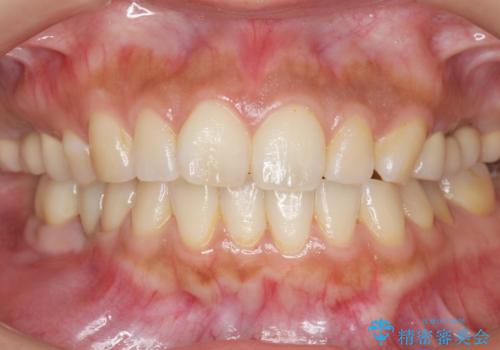

自然な仕上がりと咬み心地に喜んで頂けました。

「予算を抑えてしっかりとした治療が受けられた」とご満足頂けました。

クラウンの種類:ベレッツァクラウン